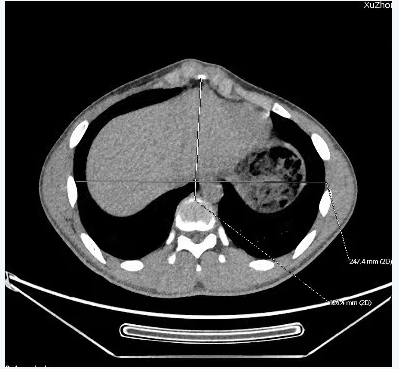

微创鸡胸反NUSS手术适应证:①CT Haller指数<2.30;②存在与鸡胸相关的心肺功能异常;③支具治疗无法耐受或失败,寻求微创手术治疗;④心理健康受到影响,寻求手术治疗。

胸部CT Haller指数测量